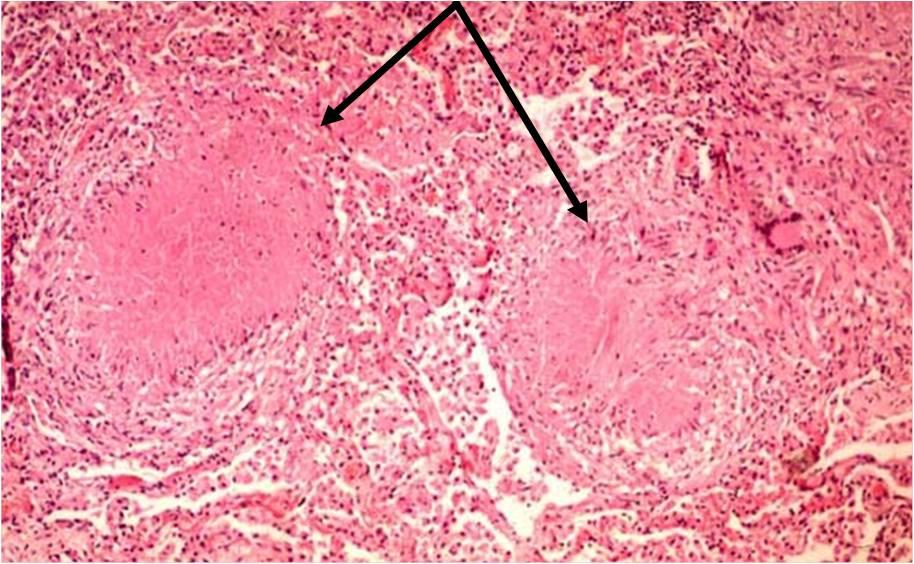

77.下列有關細胞壞死(necrosis)的敘述,何者錯誤?

(A)壞死細胞的細胞質在H&E染色較正常細胞嗜鹼性(basophilia)

necrosis:DNA、RNA下降、denatured protein↑→嗜酸